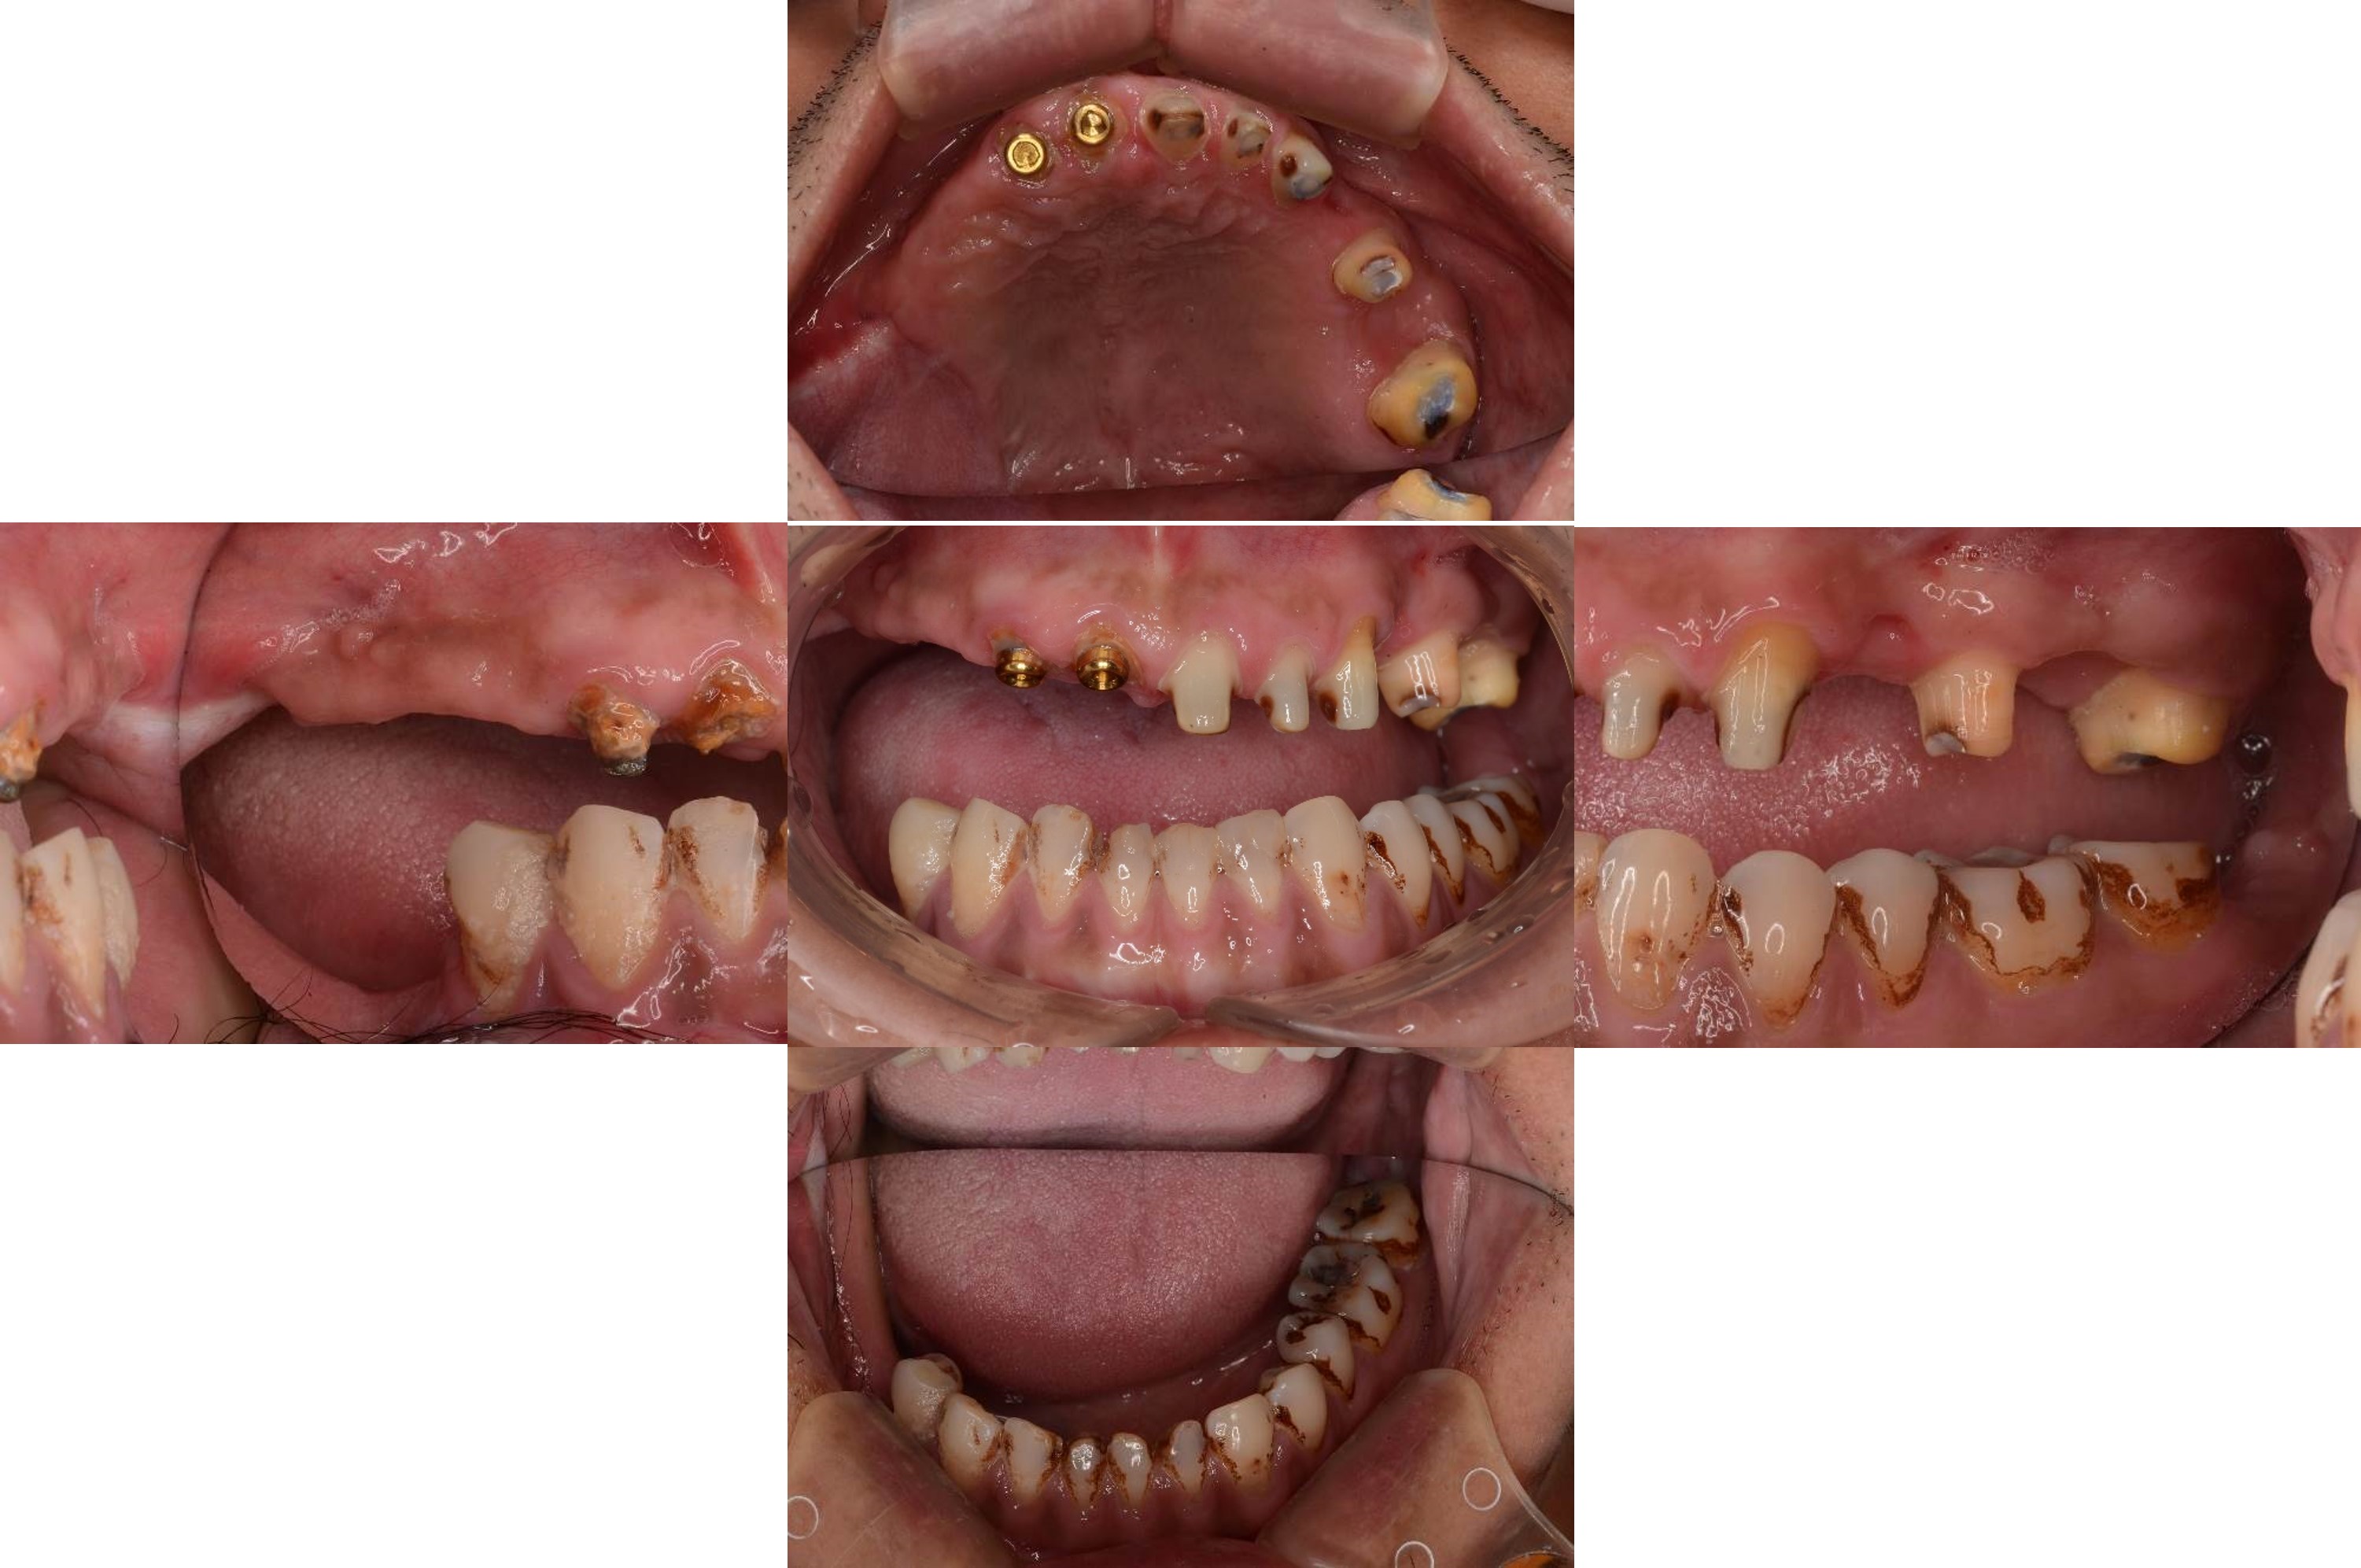

治療前上下顎因口外手術,造成咬合喪失

治療前,咬合喪失,磨耗

口外分析診斷,口外手術造成臉不對稱

治療前,殘根與牙周支撐不良